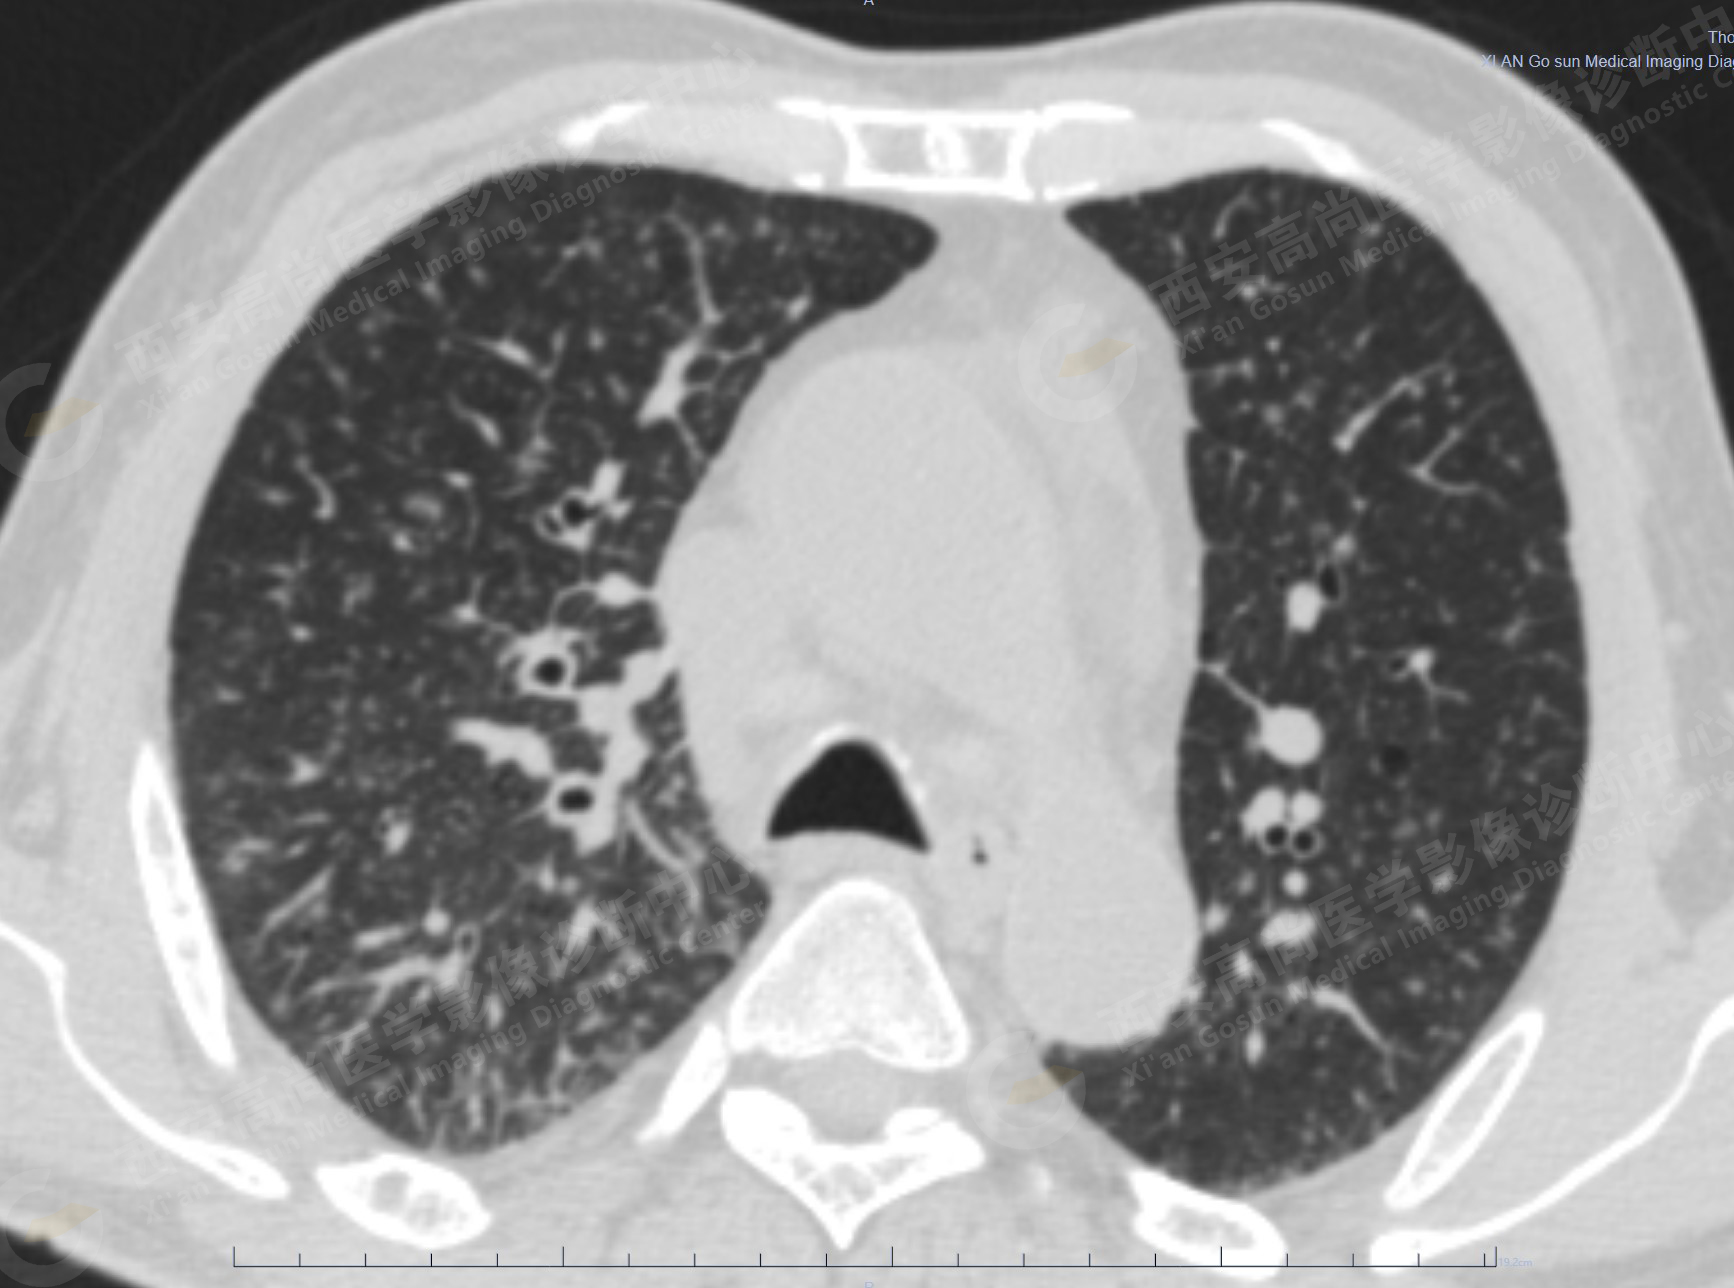

1.以下為肺內原發(fā)灶

1.右肺中葉內側段軟組織結節(jié),呈淺分葉狀,邊緣可見毛刺及胸膜牽拉征,呈FDG代謝異常增高,考慮為周圍型肺癌。

2.雙肺內彌漫性分布大小不等實性小結節(jié)灶及粟粒狀高密度影,均未見FDG代謝明顯異常增高,均多考慮為癌性淋巴結炎及轉移性病變。